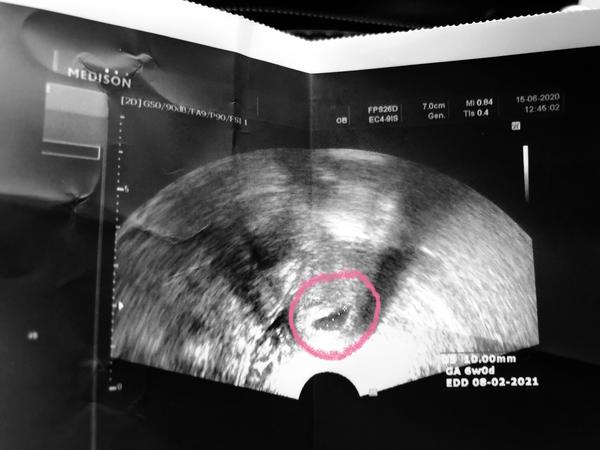

Ale uz to ustava. Pristi tyden jdu na dalsi kontrolu, uz by mel byt zloutkovy vacek, ted zatim je takova bublinka❤️

@tynka2904 byla jsem včera na pohotovosti, dělali ultrazvuk a brali krev. Byl vidět váček, aleje to bud a nebo a zítra jdu na kontrolu. Já mám hcg v pondělí jen 1700, včerejší se dozvím ve čtvrtek, ale už tomu naději nedávám 🙄.

@tynka2904 krvaceni uz ustalo, na kontrole byl porad gestacni vacek, z pondeli na utery hcg stouplo. Tak uvidime v pondeli na další kontrole.

@carolinca88 No ja dnes jela do nemocnice.. Zacla jsem krvacet.. Ale vse je v poradku, zustanu tu tri dny. Na ultrazvuku videla i malinkaty tlukot srdicka❤️

Ja jdu v pondeli na ultrazvuk, uz by mela byt videt fazolka❤️❤️❤️